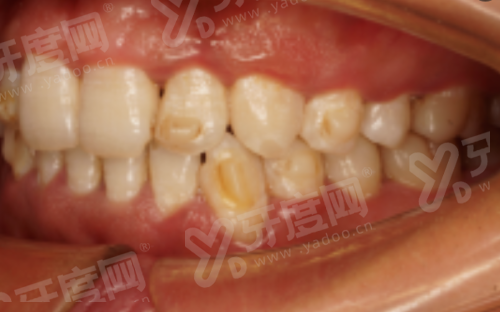

1、邵阳雅贝康口腔医院医院引进了数字化口腔CBCT设备,能够清晰地显示牙齿、牙槽骨等口腔内部结构,为种植牙、牙齿矫正等治疗提供精细的影像支持,提高治疗的正确性和成功几率。

2、邵阳雅贝康口腔医院采用数字化种植技术,通过3D导板导航进行种植手术,手术创伤小、修复快,大大减轻了患者的痛苦,让种植牙过程更加舒适。

3、邵阳雅贝康口腔医院拥有精良的口腔综合治疗台,配备了完善的诊疗设备和辅助设施,能够满足各种口腔疾病的诊断和治疗需求,为患者提供高质量的医疗服务。